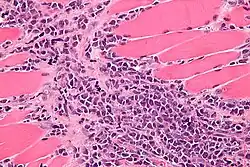

Micrograph of a myeloid sarcoma within muscle. H&E stain.

A myeloid sarcoma (chloroma, granulocytic sarcoma,[1]: 744  extramedullary myeloid tumor) is a solid tumor composed of immature white blood cells[2] called myeloblasts. A chloroma is an extramedullary manifestation of acute myeloid leukemia; in other words, it is a solid collection of leukemic cells occurring outside of the bone marrow.